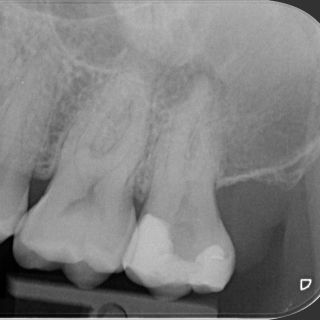

Profesionální nástroje SC-PRO z nikl-titanové slitiny jsou navrženy pro efektivní, bezpečné a šetrné ošetření kořenových kanálků. Jejich moderní konstrukce s adaptivním...